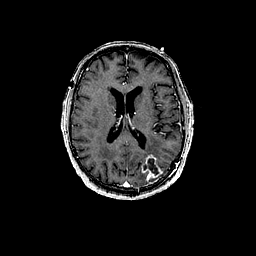

Glioma overlay -- Slice #68

[Home][Help][Clinical] Slice 68